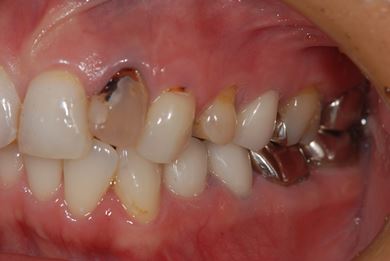

| 性別/年齢 | 女性 / 34歳 | ||||||||||||||||||||||||||||||||

| 主訴 | 現在痛みはなく、前歯の汚れを治したい。奥歯はブリッジを考えている。審美を考えているが、今治療をしたいというよりは、セラミックなど詳しいことがわからないので、計画や説明を伺いたい。 | ||||||||||||||||||||||||||||||||

| 治療方針 | 上前歯部分、セラミック治療にて審美的回復を行う。 | ||||||||||||||||||||||||||||||||

| 治療内容 | オールセラミッククラウン3本(オールセラミック用土台3本)、メタルボンドセラミッククラウン1本 | ||||||||||||||||||||||||||||||||

| 総治療費 | 562,800円 | ||||||||||||||||||||||||||||||||

| 治療期間 | 8ヶ月 |